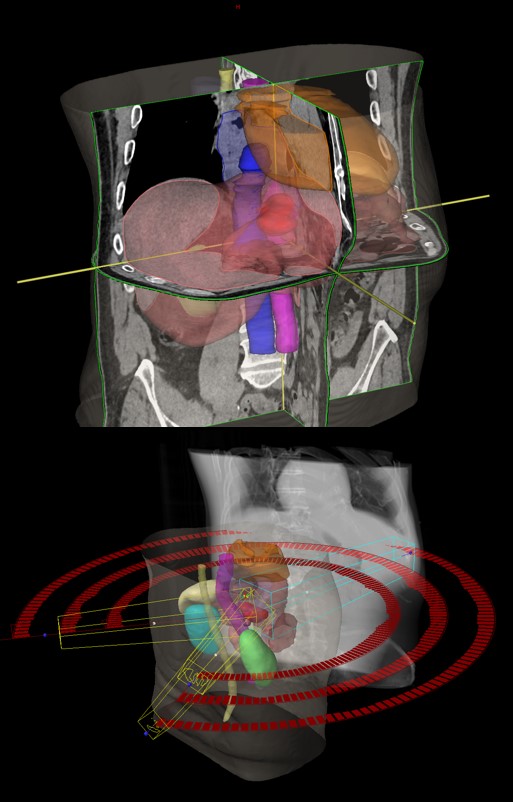

SBRT ppt recidivum locoregionalis tm oesophagei (30.09.2020. - 07.10.2020., TD 35 Gy/5 fr.)

SBRT lymphonodi intraabdominalis (22.11. - 26.11.2021.)

SABR meta hepatis (16.03.-24.03.2023.)